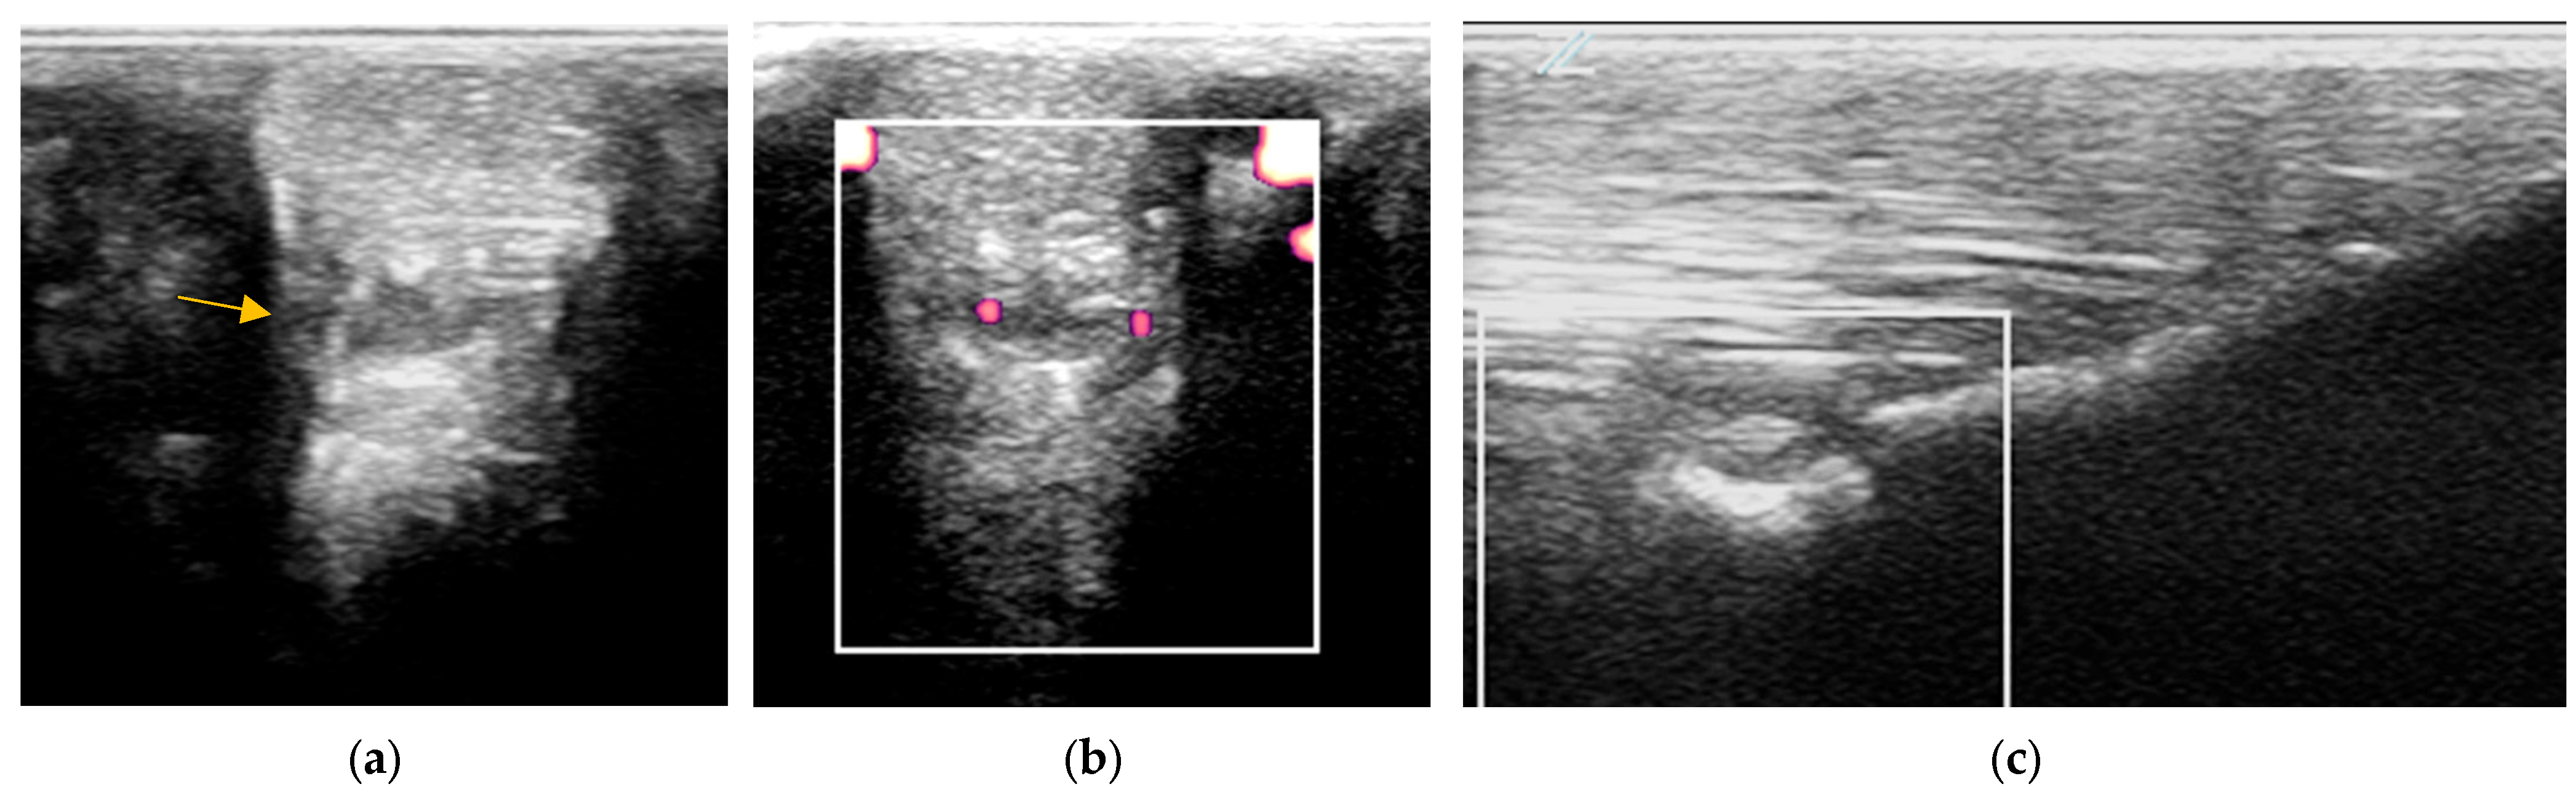

2.3.1. B-Mode Ultrasonography

2.3.2. Power Doppler Examination

2.3.3. Radiography